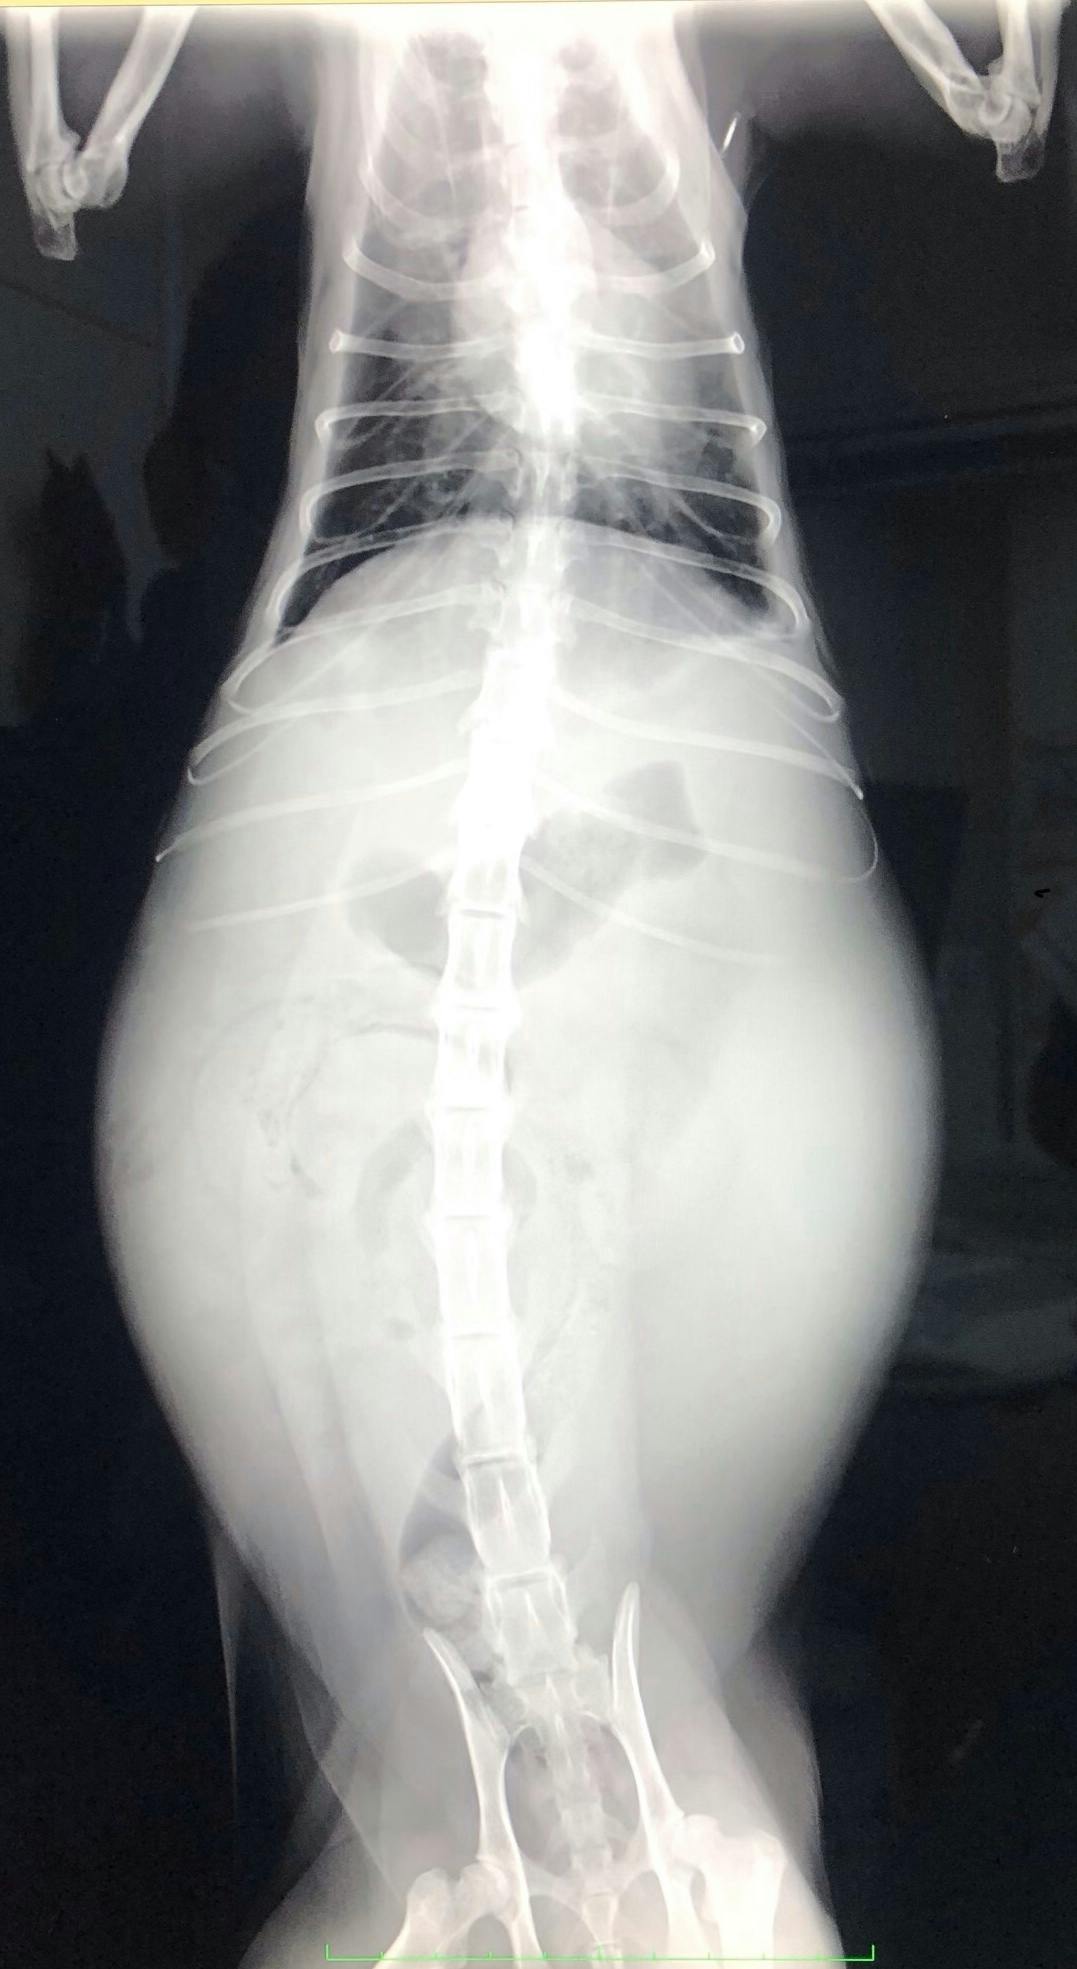

FIPという診断を受けた時に、あらゆる手段を使いこの病気について調べました。動物病院の先生やネットで調べた結果、外猫・野良猫のほとんどが持っているコロナウイルスが突然体内で変異し、FIPウイルスになるということが分かりました。FIPウイルスは一度発症してしまうと元に戻ることはありません。原因はストレスのことが多いと言われており、ずら丸にストレスを与えてしまっていたと日々嘆くばかりです。現在の症状としては腹水・胸水の貯留、食欲減退、便秘、黄疸、脱水症状です。動物病院への通院で脱水症状については収まりを見せていますが、その他は改善の兆しが見えてきません。

ずら丸の腹水が溜まっているのを見た際、リンパ癌や心臓の病気など様々な病気を疑いました。しかし考えていたよりも状況は重く、不治の病と言われるFIPでした。世界中にFIPで苦しんでいる猫、オーナー様はいらっしゃいます。MUTIANの治療で完治し、1つの道しるべとすることが出来れば、FIPの診断で悲しむ方は減るのではないかと思います。